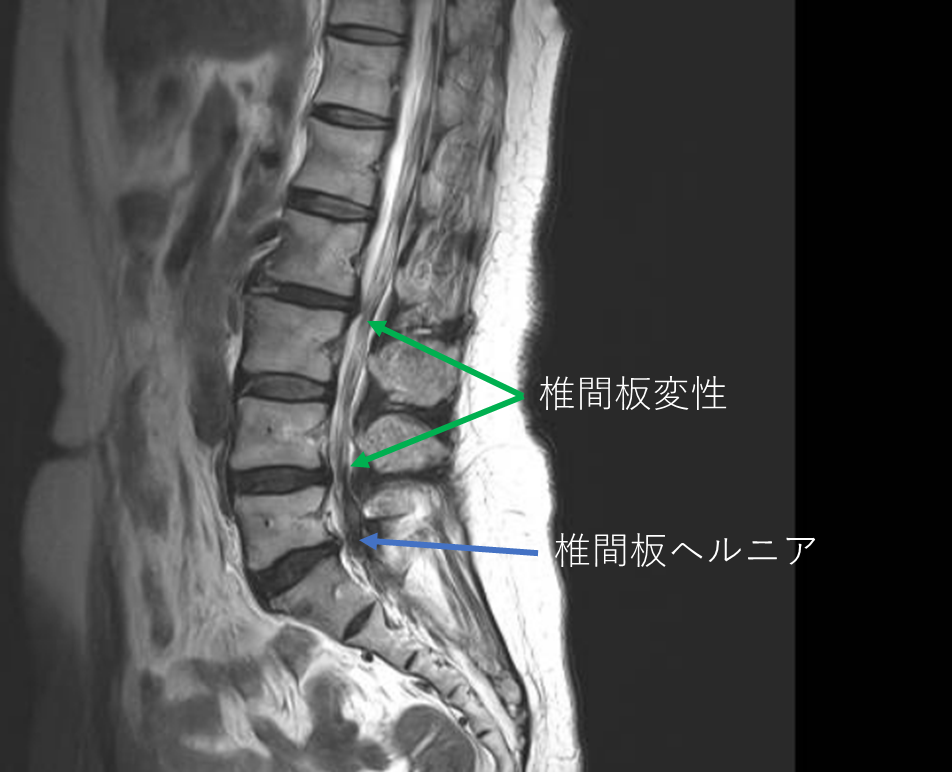

画像及び所見について

- L2/3,4/5,5/s-椎間板変性

- L5/s-椎間板ヘルニア

- L5/s-線維輪断裂

以上の事が画像上認められます。

・L2/3,4/5-椎間板変性を認め、予防的側面から

・L5/s-椎間板ヘルニアを認め、主症状の原因の可能性が高い